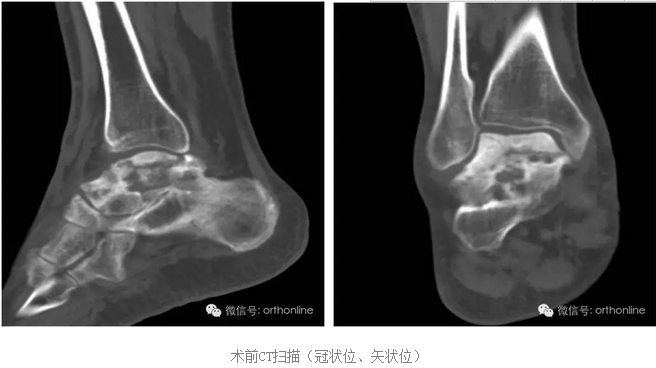

创伤引起的距骨塌陷性坏死一直是医学界面临的难题,治疗手段非常有限,目前只能采用以牺牲踝关节生物学功能的胫-距-跟植骨融合来缓解病人的痛苦,严重影响患者生活质量。

针对上述问题,由第三军医大学西南医院唐康来教授牵头,中国科学院重庆绿色智能技术研究院、物质结构研究所、金属研究所、化学研究所、理化技术研究所等十个单位协作攻关,分别从3D打印设备与专用材料、个体性产品开发与临床应用方面进行研究,研制了世界上首个3D打印的具有生物学功能的个性化距骨假体,于2016年7月4日在重庆第三军医大学西南医院成功应用于创伤引起的距骨塌陷性坏死病例。

塌陷性距骨坏死一直是踝关节假体置换的绝对禁忌症,该假体打破了常规,为塌陷性距骨坏死提供了非常好的选择。